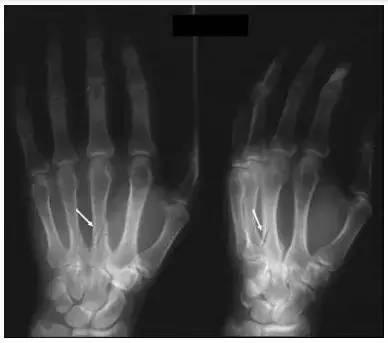

在保罗的案例中,骨间产生不规则的分离,使得骨产生延对角线的下移,从而可能在恢复中使情况更为复杂化。